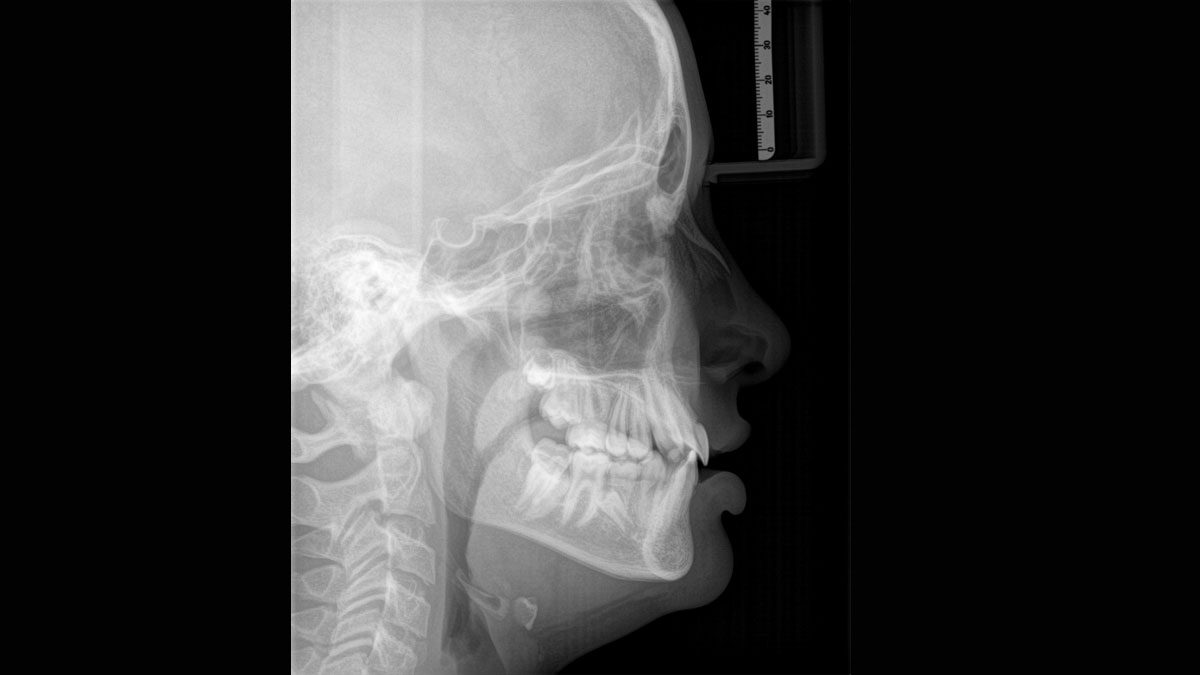

Axeos – the 2D/3D specialist system with a large volume and high image quality for practices with a broad treatment offering. Developed together with dentists and clinicians, Axeos provides the fullest range of functions out of all Dentsply Sirona extraoral X-ray devices. In addition to excellent image quality and tailor-made 3D volume sizes, the dental imaging device is fully optimised for enhanced patient comfort. Axeos not only provides quality in performance and comfort, but also with its award-winning design thanks to the integrated bite block accessory cabinet and ambient light.

For exceptional panoramic images with high sharpness. You can choose an optional right or left cephalometric arm, which can be retrofitted at any time